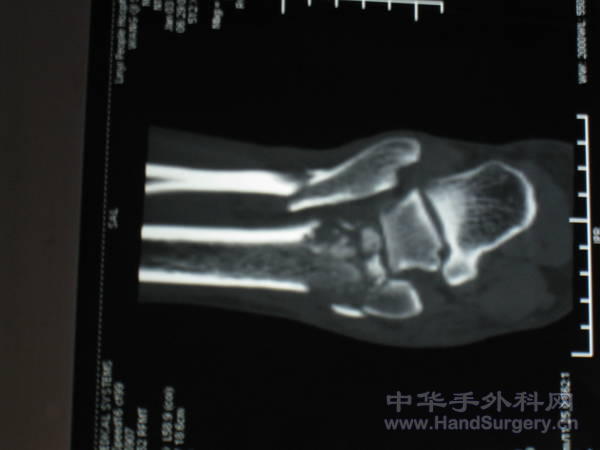

pilon骨折一例-手足外科魏宝富主任作品

pilon骨折在哪做都是高难度手术,骨性支架的建立应该最重要,皮肤缺损对手足外科大夫来讲已经不是什么难题 ,希望看到踝关节关节面的x线或ct。

魏主任:你的手术做的很好,但是不知关节面是如何处理的,植骨了吗?是急症做的还是消肿以后做的?切口愈合如何?还有外侧的关节面好像没有处理?

希望能看到术后CT片,了解关节面的情况。个人愚见,这种情况用外架固定是否更合理?